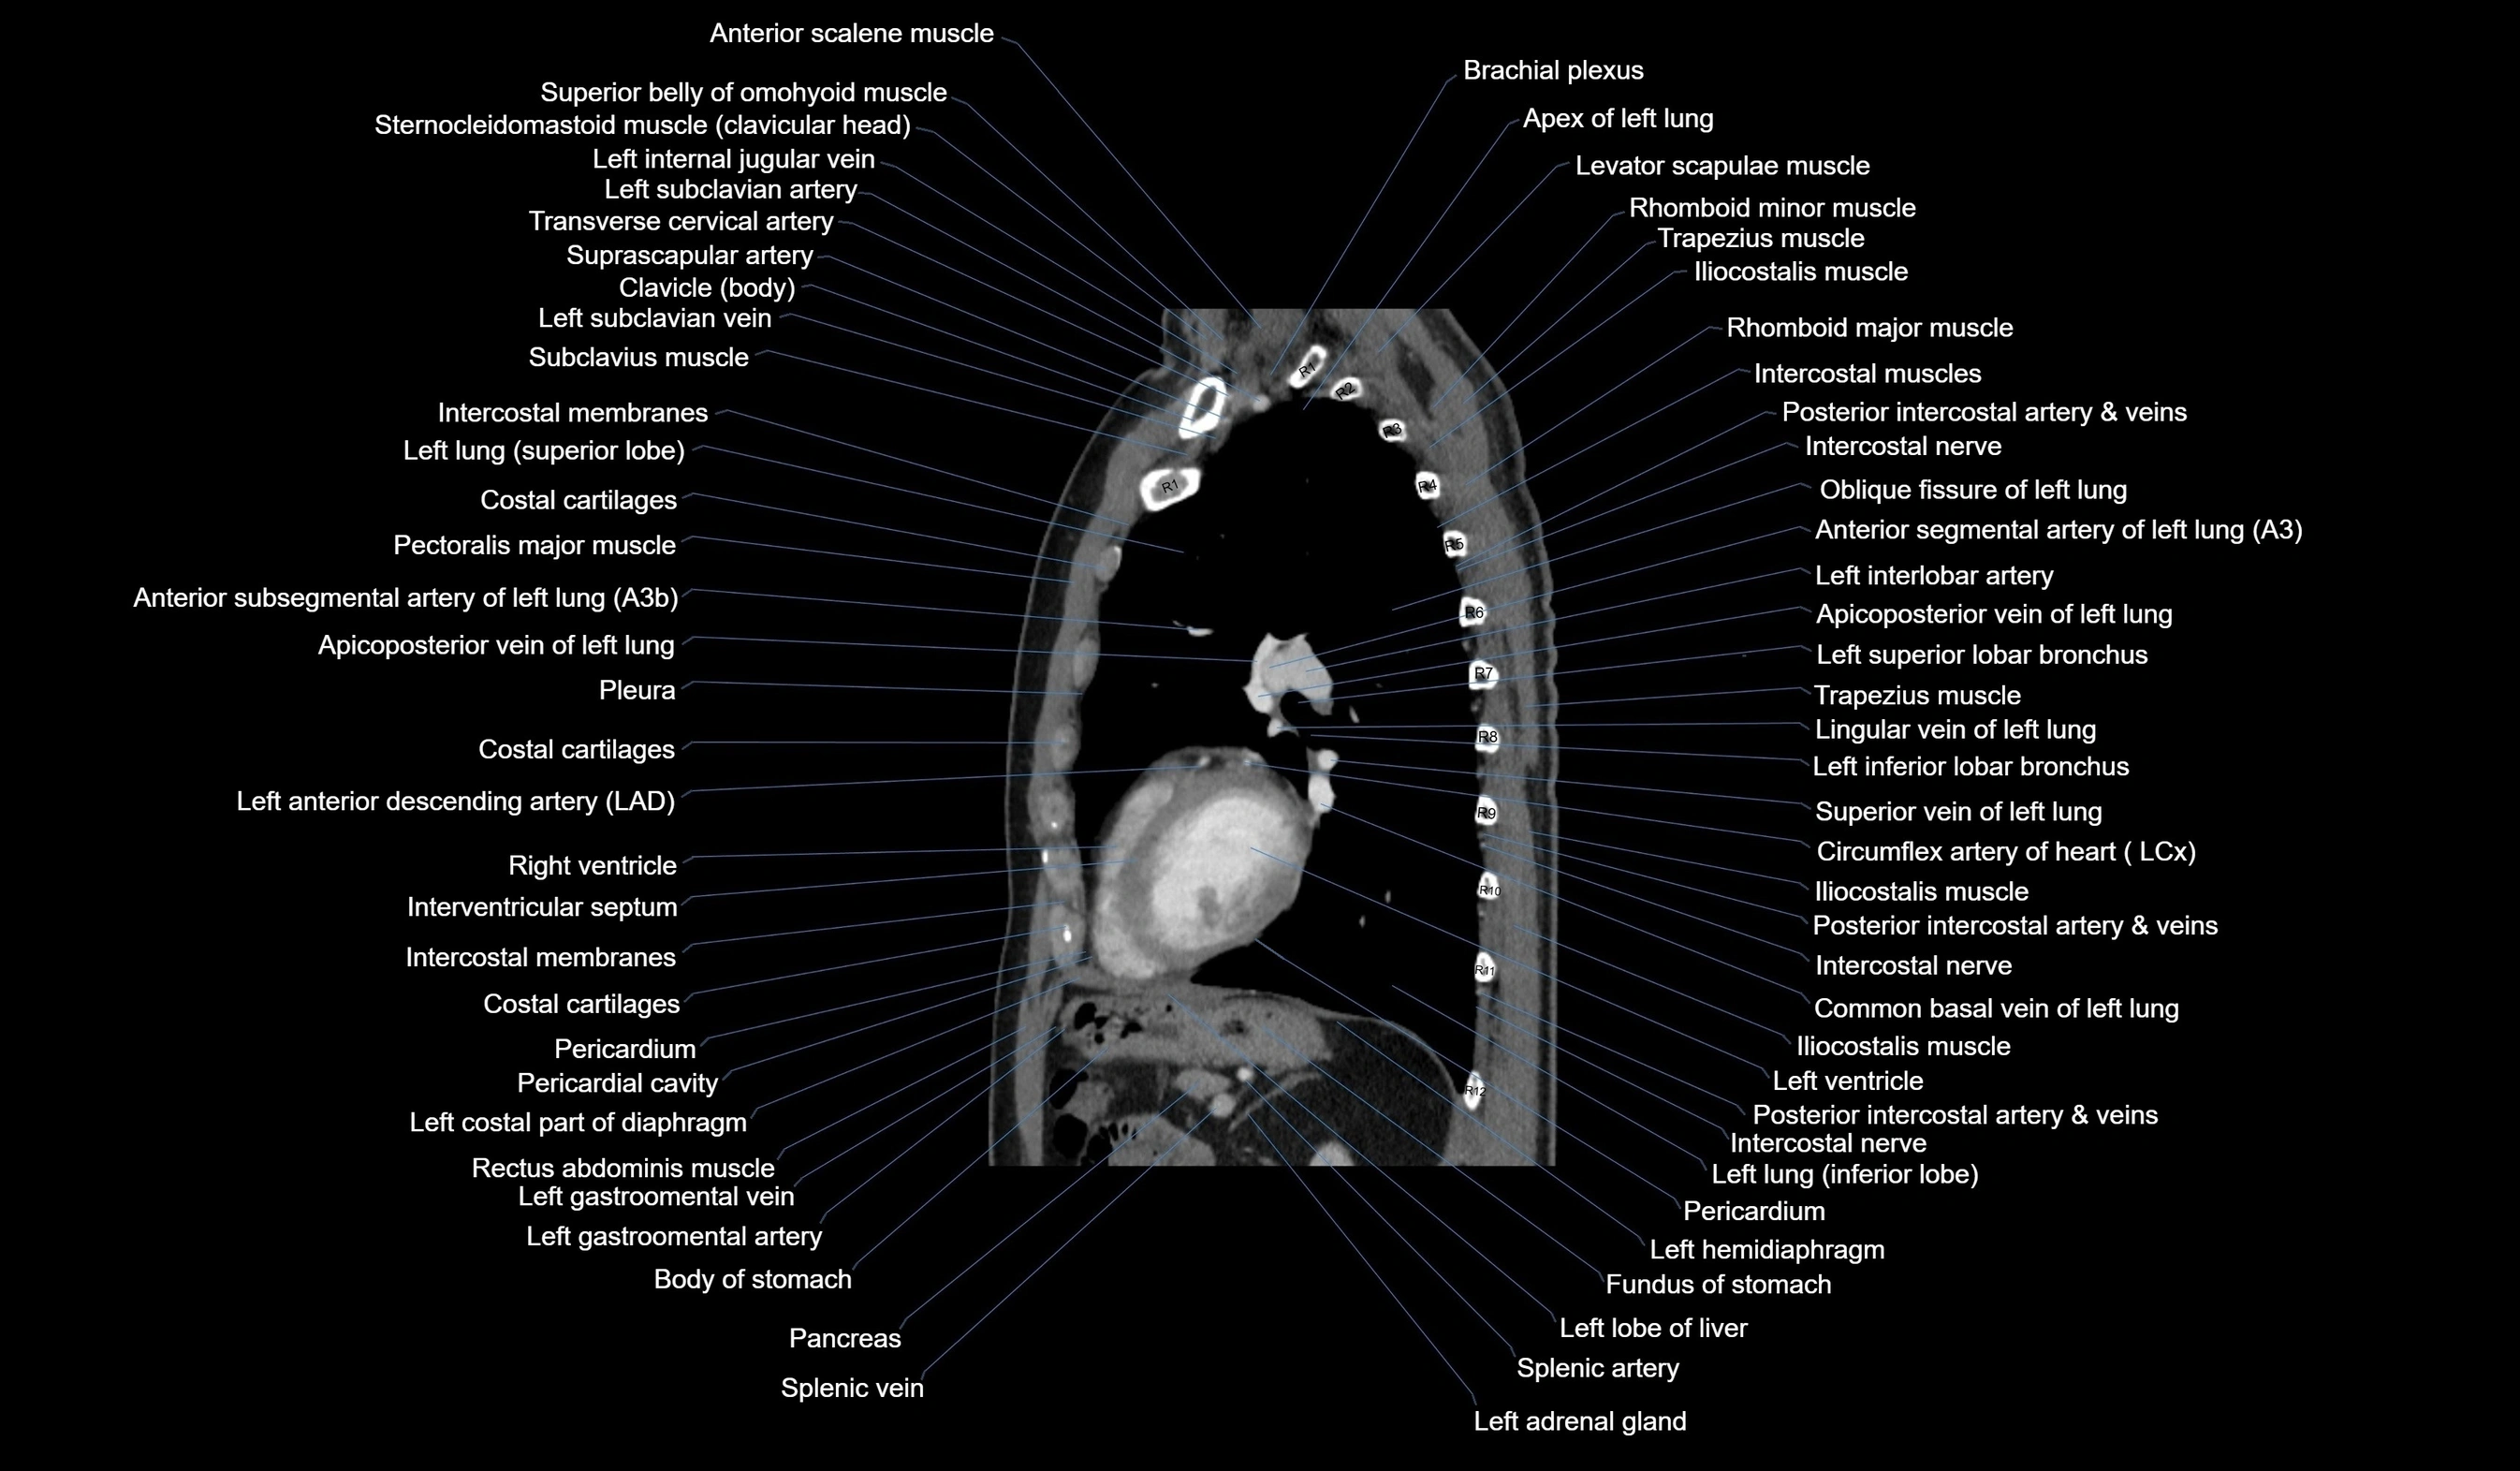

CT images